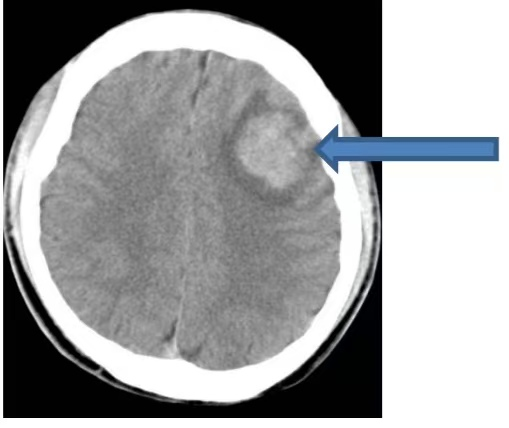

在今年的出院隨訪工作中,我們遇到了這樣一個病例:一位此前被診斷為“顱內海綿狀血管瘤”的年輕人,因癲癇再次發作接受了外科手術,切除了導致癲癇的病灶。這個致癲灶就是導致癲癇發作的“隱形推手”——顱內海綿狀血管瘤。以下通過這個病例,我們逐步揭開“顱內海綿狀血管瘤”的神秘面紗。 這位20歲的小伙在吃飯時突發肢體抽搐、意識喪失、跌倒,意識轉清后完善頭CT發現“左側額葉出血”。當時我們懷疑是瘤卒中,也就是說,小伙顱內長有一個腫瘤,且出血局限于腫瘤內部(如下圖CT所示)。 為了進一步明確腫瘤性質,隨后進行的磁共振檢查顯示:腦內存在多發異常信號影,影像科考慮為多發海綿狀血管瘤。這并非傳統意義上的實質性腫瘤,海綿狀血管瘤是一種血管畸形。在這些血管瘤中,最大的一個位于額葉,且內部發生了出血(如下圖所示)。 最后又完善了磁共振增強檢查,考慮左側額葉血管畸形伴出血(如下圖)。 經省內專家會診,最終診斷:顱內海綿狀血管瘤,并建議使用抗癲癇藥物。 下面,我們來簡單了解一下海綿狀血管瘤: 一 什么是海綿狀血管瘤(CMs) 中樞神經系統海綿狀血管瘤(CMs)是一種先天性血管畸形,分為家族遺傳病例和散發病例。其在顱內血管畸形中占比10%-25%,僅次于腦動靜脈畸形。CMs具有一定的生長能力,在對家族型腦內CMs病例的定期隨訪中發現,每個病例每年可能新增0.4 - 2.7個腦內CMs病灶。 家族遺傳型病例與基因突變相關,散發病例可能與放射線、外傷、顱內感染等外界誘發因素有關。 二 CMs的臨床表現 最常見的臨床表現為癲癇、腦內出血和無近期出血影像學證據的局灶性神經功能缺損。還有20%-50%的腦內CMs屬于無癥狀性,常因腦磁共振的廣泛應用而被偶然發現。 三 CMs的影像學診斷 CMs在CT上表現為邊界清楚的圓形或類圓形的高密度影。CT對體積較小的腦內CMs不敏感,并非腦內CMs最好的檢查手段,臨床上更適合用于急性血腫、占位效應和腦積水的緊急診斷。但反復CT檢查的電離輻射存在促進增加新發腦內CMs的風險,所以當CT初步懷疑腦內CMs后即應進行MRI檢查,且在隨訪觀察中繼續選擇磁共振。 MRI對腦內CMs的檢出敏感性極高,且無創,被推薦為首選的影像學檢查方法,能夠顯示常規序列無法顯示的微小病灶。 DSA檢查中CMs病灶一般不顯影,故DSA在腦內CMs診斷中的作用非常有限。 四 顱內海綿狀血管瘤的治療 外科手術治療 外科手術被認為是腦內CMs最有效的治療方式,但手術切除的指征,仍存在爭議。對于無癥狀的腦內CMs,尤其位于功能區、深部或腦干的無癥狀病灶,一般主張采取保守治療。 手術是控制癲癇發作最有效的方式,可優先考慮手術切除病灶及周圍含鐵血黃素沉積帶;若單藥治療無法控制癲癇發作,也可考慮手術。 立體定向放射外科治療 立體定向放射外科可作為一種治療選擇,應用于功能區、腦深部及腦干癥狀性腦內CMs;無癥狀的和易于手術的癥狀性腦內CMs,均不建議選擇。 內科處理 顱內海綿狀血管瘤相關性癲癇的藥物控制率可達到50%-60%,因此患者一旦確診,即需開始使用抗癲癇藥,同時要注意避免易誘發癲癇的藥物和活動。 腦內CMs相關頭痛的發生率可能高達52%。對于同時患有腦內CMs且符合偏頭痛診斷標準的患者,建議進行標準的偏頭痛治療,非甾體類抗炎藥是安全有效的選擇。 特殊群體顱內CMs的管理 通常情況下,腦內CMs患者是可以選擇妊娠的,但需要進行遺傳咨詢,對于CMs相關性癲癇患者需要調整抗癲癇藥物以降低致畸風險。 10歲以下兒童更容易因輻射誘發新生腦內CMs,所以應盡可能避免反復CT和X線檢查。